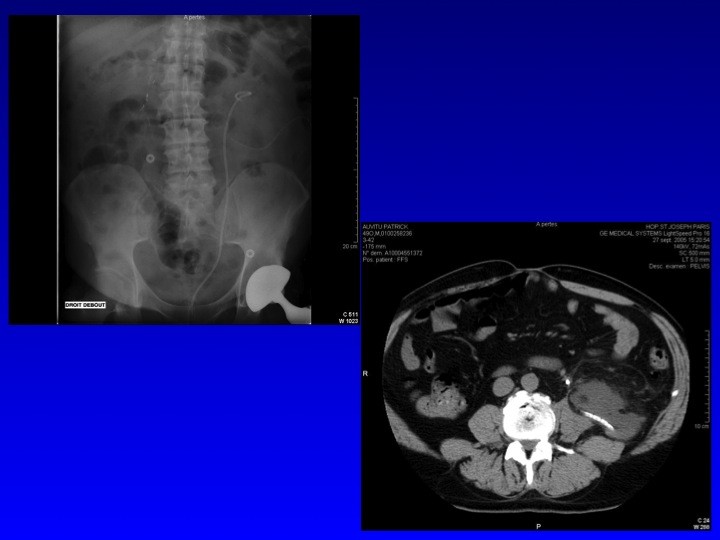

Prise en charge des petites tumeurs rénales en 2011 : diaporama 2